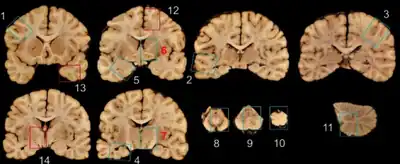

NINDS/NIBIB-Minimum recommended brain regions for evaluation for CTE. The following sections from the NIA-AA blocking scheme are recommended for p-tau immunostaining in evaluation for CTE (blue rectangles). In the cortical sections (blocks 1–5, 12, 13), the depths of the cortical sulci should be included in the section. 1 Middle frontal gyrus, 2 superior and middle temporal gyri, 3 inferior parietal lobule, 4 hippocampus, 5 amygdala and entorhinal cortex, 6 basal ganglia at level of anterior commissure with basal nucleus of Meynert, 7 thalamus, 8 midbrain with substantia nigra, 9 pons with locus coeruleus, 10 medulla oblongata, 11 cerebellar cortex and dentate nucleus; additional sections if high suspicion of CTE (red rectangles): 12 superior frontal gyrus, 13 temporal pole, 14 hypothalamus and mammillary body